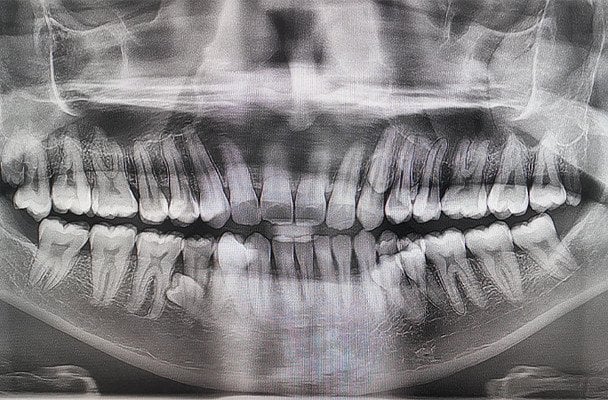

У роті рекордсмена нарахували 42 зуби — на десять більше, ніж у середньостатистичної людини.

Як повідомляє Книга рекордів Гіннеса, чоловік має 42 зуби, що на десять більше, ніж у середньостатистичної людини, і це дозволило йому встановити світовий рекорд серед чоловіків.

За словами Пратаба, тоді він пожартував із рідними, що, здається, у нього ростуть додаткові зуби. Разом вони вирішили їх порахувати й виявили 38. Згодом рентгенівське обстеження показало, що в щелепі є ще чотири зуби, які на той момент не прорізалися.

На початку 2023 року після огляду стоматологів було офіційно підтверджено, що загальна кількість зубів у чоловіка становить 42. При цьому, за словами лікарів, більшість із них ростуть рівно та не спричиняють ускладнень.